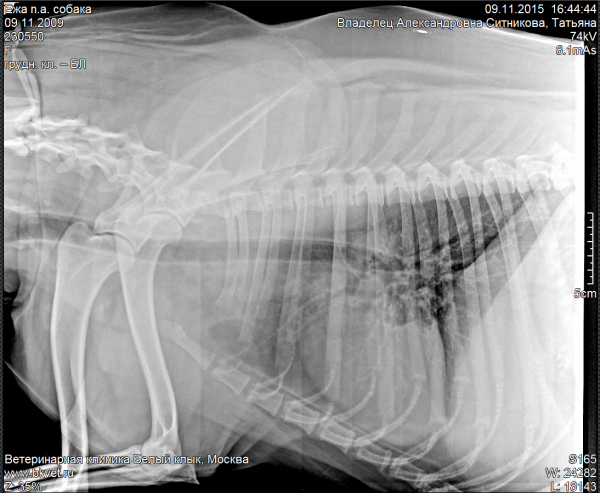

Но к нашему большому сожалению здоровье у Ежи оказалось в довольно запущенном состоянии... Хронические ринит никак не проходит, периодически обостряется цистит. При этом возникают еще каки-то симптомы, которые дают опасения подозревать нарушения функции щитовидной железы.

| Rentgen 112015.PNG | 270.46 КБ |